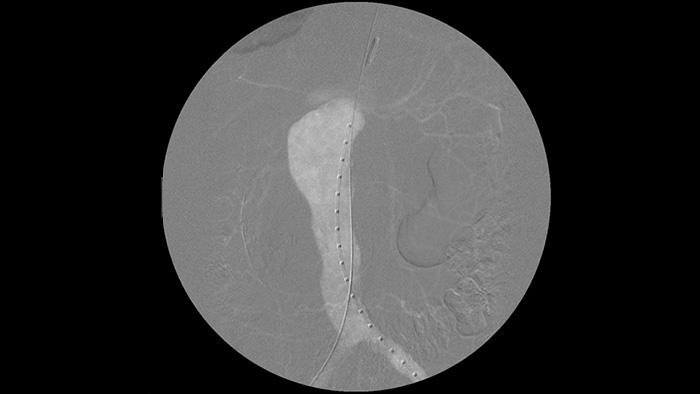

La angiografía por sustracción digital (DSA) se utiliza en procedimientos vasculares intervencionistas para visualizar claramente los vasos sanguíneos mediante la eliminación de estructuras que puedan oscurecer la visibilidad de los vasos. La fluoroscopia Roadmap superpone una imagen de contraste sustraída previamente adquirida en la fluoroscopia en tiempo real, lo que le permite rastrear un dispositivo sin volver a inyectar el contraste.

Es más fácil ver cable guía en comparación con nuestro antiguo sistema. Ahora puede ver la punta y el ángulo del cable que se desplaza, incluso con cables de 0,014 pulgadas.

Esto se debe a que Zenition compensa la parte metálica y la parte que se mueve."